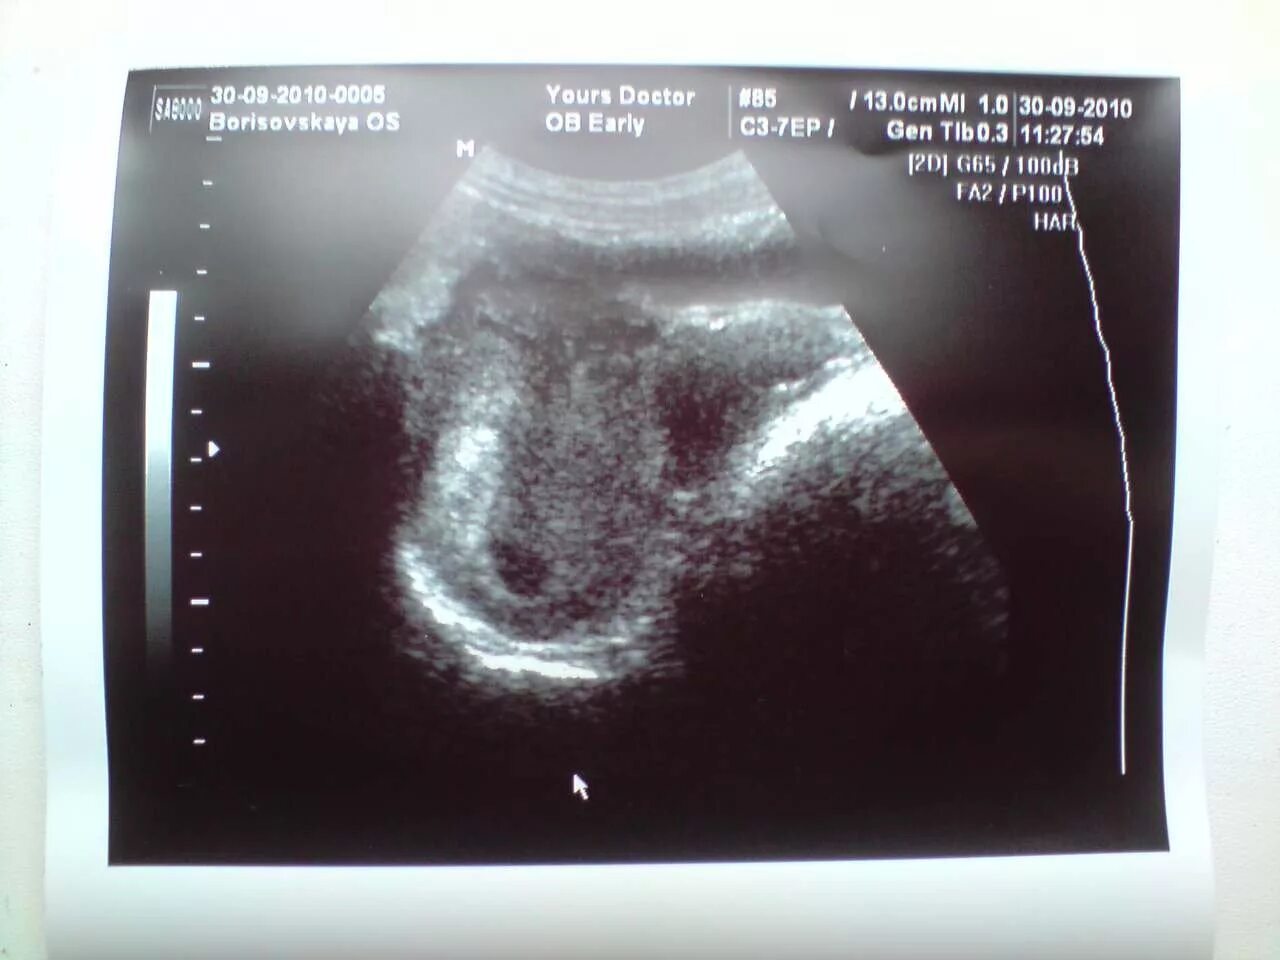

Беременность 5 мм